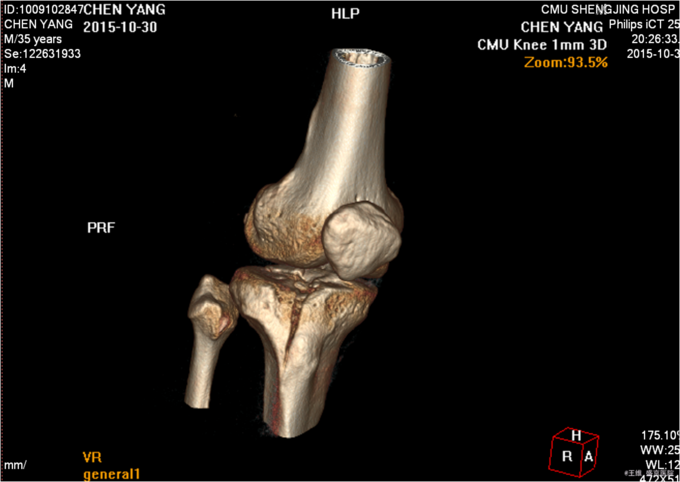

主诉:车祸致右膝部疼痛肿胀活动障碍5小时 现病史:患者及家属代述患者于2015年10月30日下午5点时在走路时被汽车撞伤发生车祸,导致右膝部疼痛肿胀活动障碍,当时无昏迷,送至沈阳中医4院,行DR及影像学检查示:右胫骨平台骨折,右12肋骨骨折。家属为行进一步治疗来我院就诊。经门诊检查后收入我科。患者病来,意识清醒,无头痛头晕,无咳嗽咳痰,无心慌气短,饮食正常,小便正常,大便未排,体重无变化。

患者于2015年10月30日因右侧胫骨平台骨折入院,入院后给予消肿止痛对症治疗后,于2015年11月6日在全麻下行右胫骨平台骨折切开复位内固定术,手术顺利,患者安全返回病房。术后常规给予抗炎消肿对症治疗后,待病情稳定后于2015年11月24日遵医嘱出院。